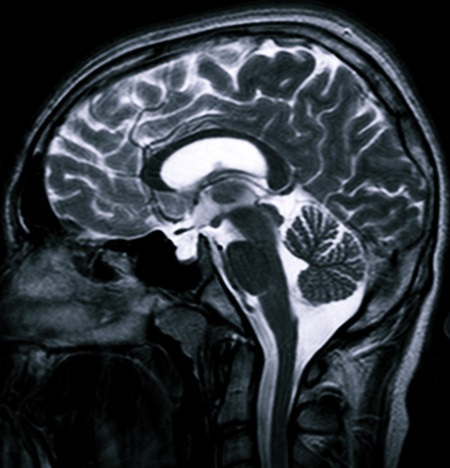

Чтобы уточнить диагноз, человека могут отправить на компьютерную томографию, рентген или магниторезонансную томографию (МРТ). Посредством такого обследования оценивается состояние гипофизарной ямки, размеры и контуры турецкого седла, наличие уплотнения дна, утолщения клиновидных отростков, определяется, имеет ли место отмирание тканей мозга, деструкция гипофиза, наличие гиперплазии и ликворного содержимого.

Все эти негативные состояния можно найти с помощью КТ или МРТ. Поэтому данные виды обследований должны быть обязательно назначены врачом при наличии соответствующей симптоматики, указывающей на вероятность развития синдрома.